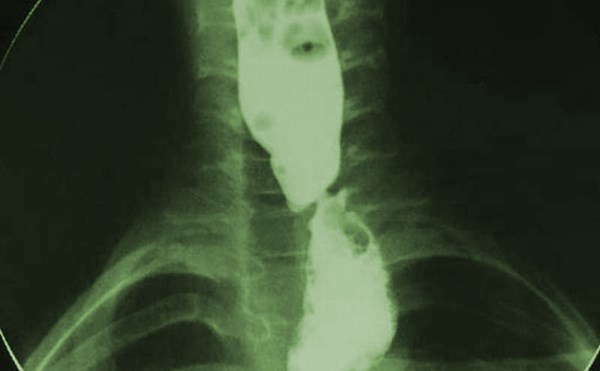

Caustic Ingestion

The patient is a 17-year-old male with a history of depression and prior alcohol abuse who presents to the emergency department with his ex-girlfriend after ingesting “Poolife Rapid Shock.”